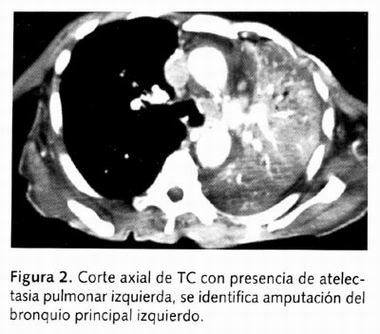

Asimismo, se le realizó una tomografía computada la cual mostró una masa ocupante de densidades heterogéneas con múltiples zonas hipodensas y líquidas; observándose colapso pulmonar junto a la misma (Figura 2), la cavidad pleural derecha mostró líquido en su interior y una zona de consolidación adyacente a ella, existe amputación del bronquio principal izquierdo. No se aprecian crecimientos ganglionares importantes en el mediastino (Figuras 3 y 4).